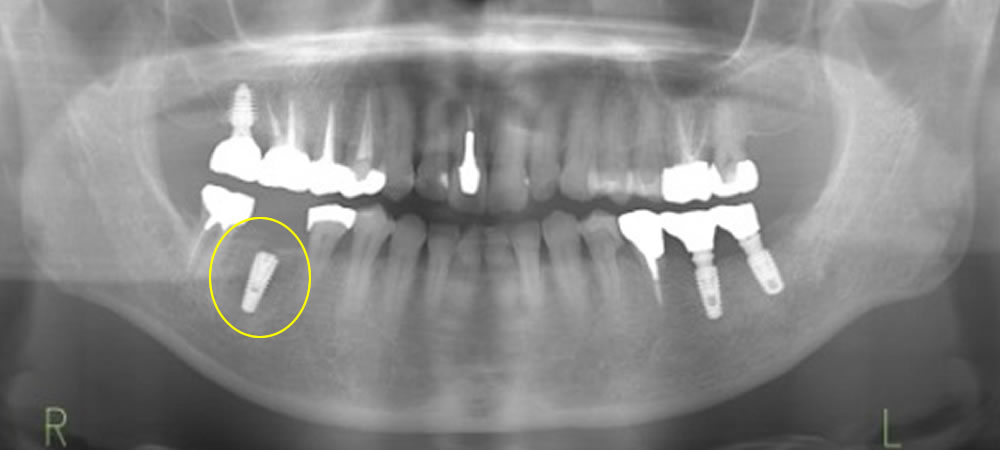

事前にブリッジを除去し、支台歯となっていた右下5・7の虫歯治療を行いました。その後、CT撮影で骨の状態を確認し、服薬内容や手術の流れをご説明したうえで、手術日を決定しました。

手術当日は、麻酔下にてインプラント埋入手術を行いました。術後1週間後に消毒・抜糸を行い、メインテナンスを行いながらインプラントと骨の結合を待ちます。